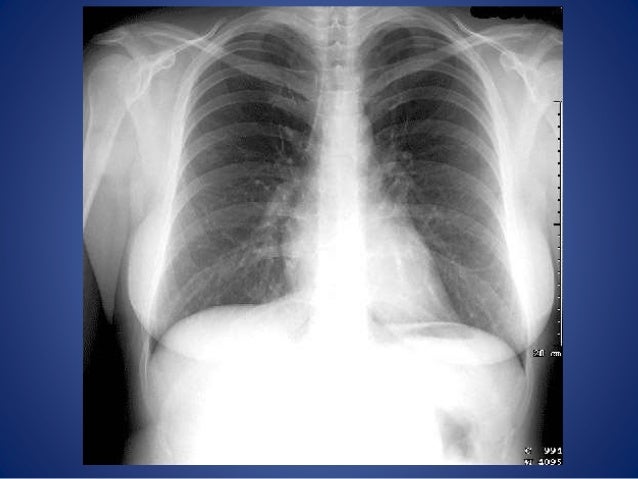

As long as the detector is not underexposed or greatly overexposed a diagnostic image will be displayed. Images will be displayed with the optimum density and contrast when the system has been set up with the required algorithm for chest imaging in our examination. One major advantage of digital radiography systems is the very wide exposure latitude. It’s the responsibility of the radiographer / technologist to select a technique that provides enough exposure to reduce the amount of noise while also adhering to ALARA/ALARP standards. Images should be repeated if relevant anatomical details or ability to see lines or endotracheal tubes in the mobile chest image cannot be distinguished because of poor positioning or exposure making the image undiagnostic. The 3-point scale for producing diagnostic images is: Image evaluation for exposure should perhaps be conducted using EI T is the EI for a given radiograph and the target exposure. Gross over exposure will result in ‘burned out’ pixels losing anatomical detail usually in the lungs. Underexposure can result in image noise, however, overexposed images will be displayed optimally on the display screen often at ten times the exposure. Digital systems generally display images with the optimum density and contrast regardless of the exposure factors. It is therefore important for the radiographer / technologist to understand Exposure Indicators (EI) and the Deviation Index (DI).